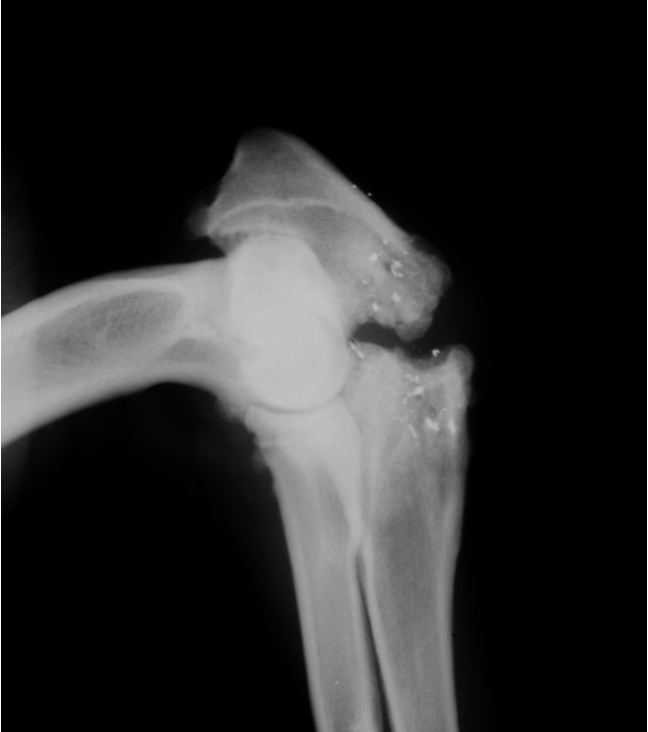

Metaphyseal osteopathy signalment

2-7 mo age

large giant breeds

systemically ill

bilateral/all 4 limbs

double physeal sign ± cuff

Metaphyseal osteopathy